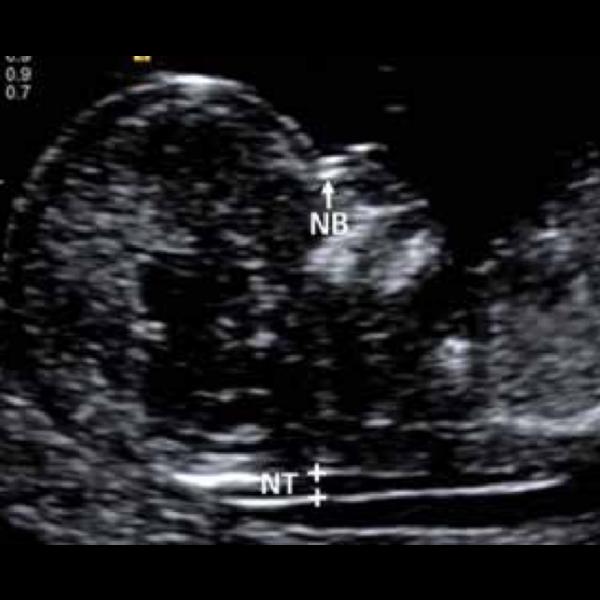

# NTNB scan near me Rohini C-8/193 sector - 8 rohi...

NTNB ultrasound

NTNB scan C-8/193 sector - 8 rohini delhi 110085, ...